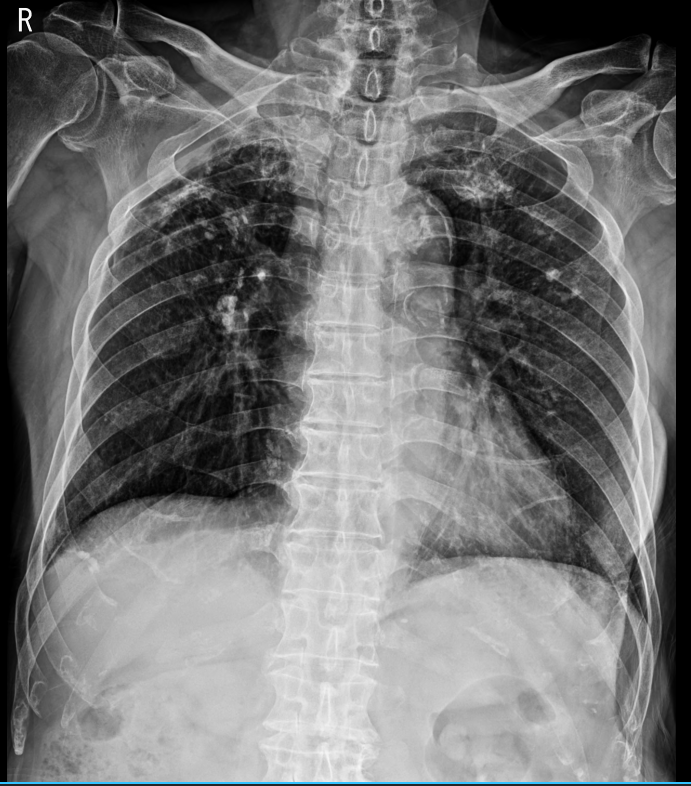

좌측의 x ray 사진은 chest PA를 오른쪽은 chest AP로 촬영한 사진이다.

한눈에 봐도 chest PA로 촬영한 것이 폐의 용적을 최대한으로 보여주기에 좀 더 선호되는 방식이고, chest AP는 환자가 서기 어려운 상황이거나 이동식 x ray 장비를 이용해야 하는 어쩔 수 없는 상황에서 촬영하는 방식이라 이해하면 편하겠다.